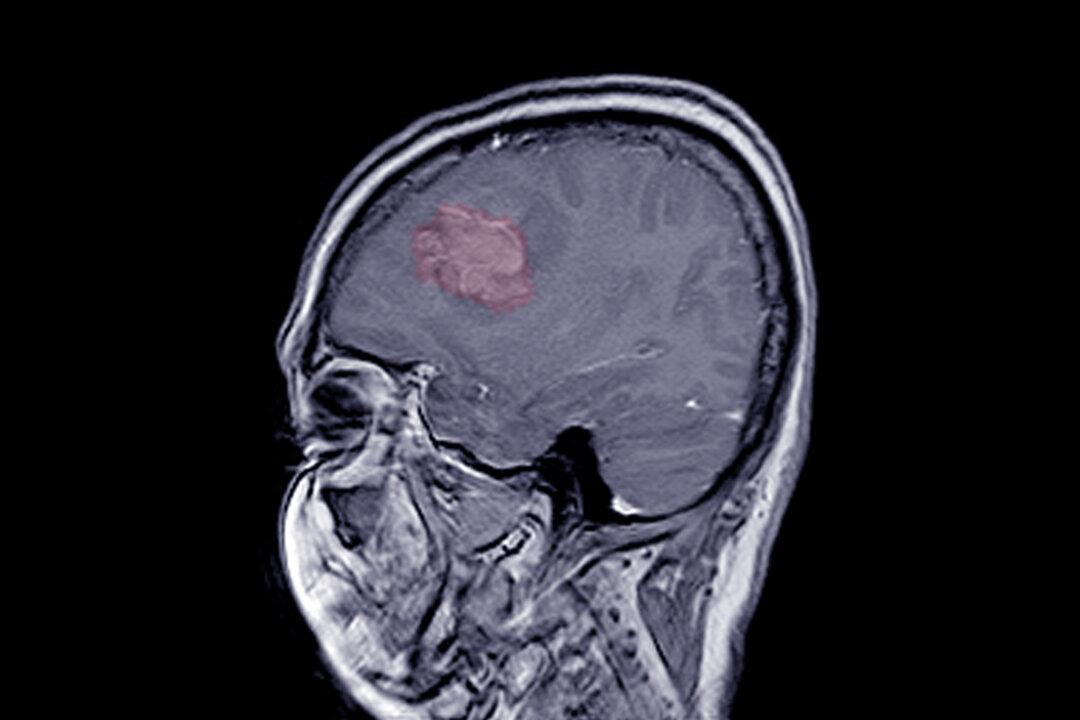

Prolonged use of certain progestogen hormone drugs, including a common injectable contraception, is associated with an increased risk of developing intracranial meningioma tumors.

In a recently published study in The BMJ, French researchers found that medrogestone, promegestone, and injectable medroxyprogesterone acetate—a widely used contraceptive known by the brand name Depo-Provera—increase the risk of intracranial meningiomas requiring surgery.